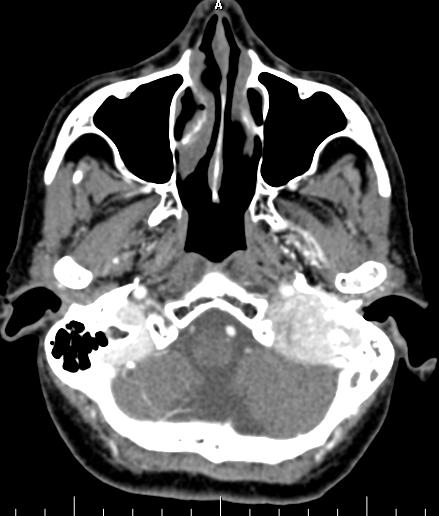

1.CT平扫呈等或略高密度,颈静脉孔扩大,邻近骨质破坏。肿瘤经颈静脉孔入颅生长时,可累及桥小脑角、中耳、脑干和第四脑室,肿瘤累及乙状窦并不少见;向颅外生长可进入颈部咽旁间隙。增强后扫描病灶呈均匀明显强化。

左颈静脉孔可见一个明显强化病灶,大小约为3.5 x 3.5 x 3.5 cm。病变导致颈静脉孔破坏和扩大。

在内侧,病变在后颅窝有颅内硬膜外延伸,使小脑皮质凹陷。

在外侧,病变延伸到中耳腔(上鼓室、中鼓室和下鼓室)和外耳道。砧骨长突、下半规管、耳蜗底回和面神经鼓室段外侧壁均有侵蚀。

病变浸润颈静脉球,并向近端颈静脉延伸。在后方,枕骨基底部和枕骨大孔的外侧被破坏。